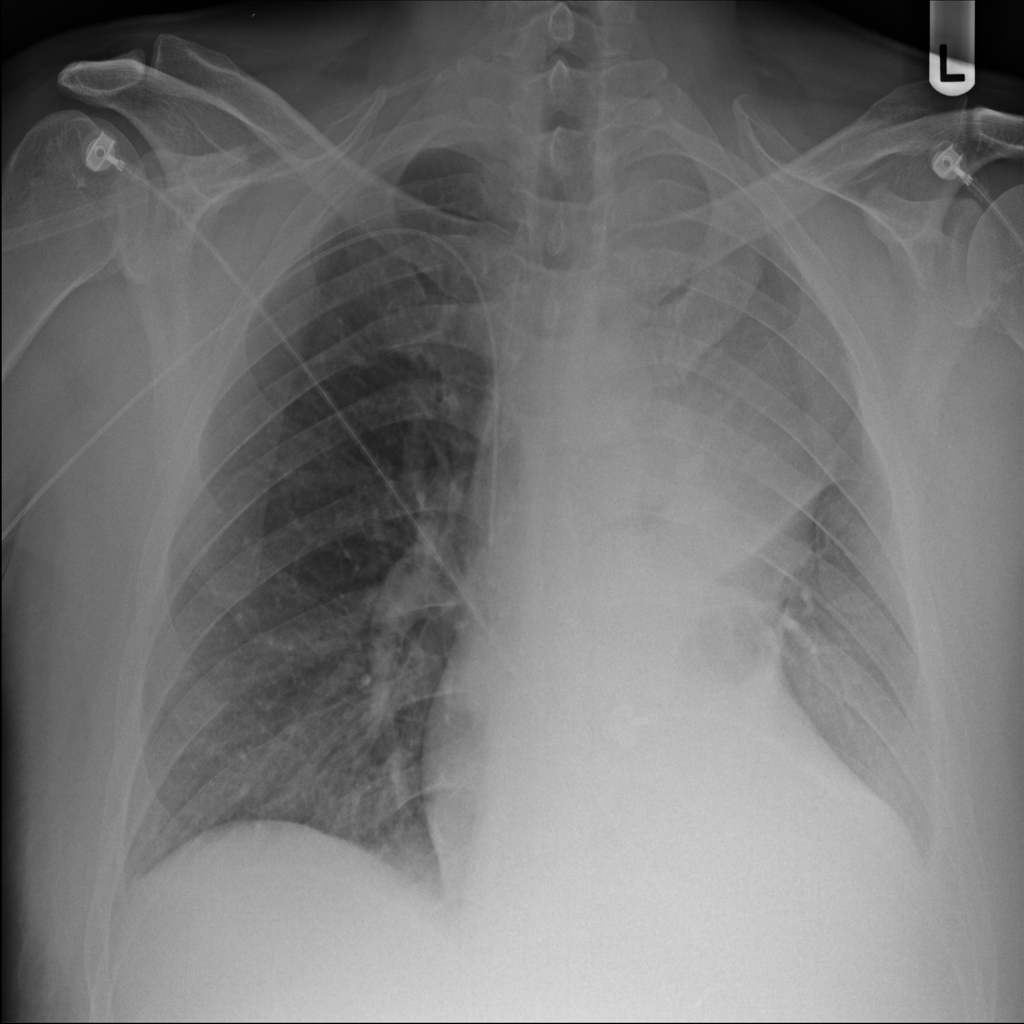

PAT-64EB · IMG-015Consolidation

PAT-64EB · IMG-015

AP